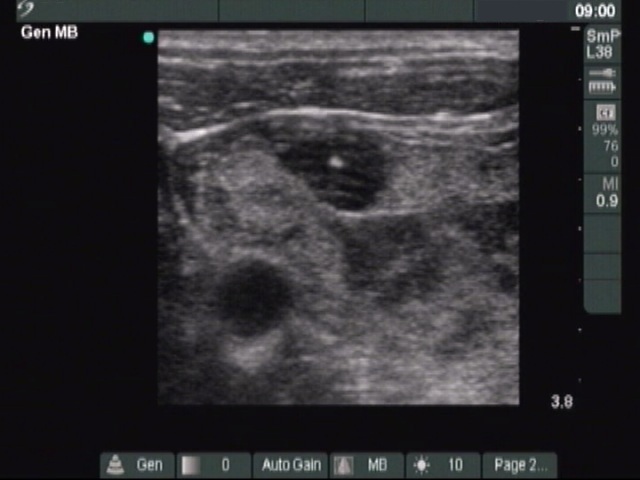

The composition of the nodule - case 353 (ultrasonographic picture 10)

Right lobe, longitudinal scan - at the end of the aspiration. Although we aspirated 23 ml cystic fluid, the size of the lesion remained unchanged.